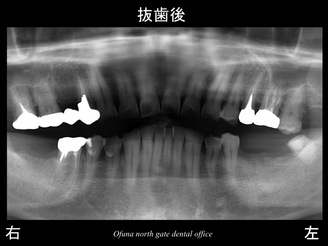

治療計画としてまず、虫歯の深い歯は保存不可能であったため、抜歯としました。

以下が抜歯後です。

抜歯後は、下顎の左右の奥歯が欠損してます。

当然のことながらこの部分では噛めないことになります。

欠損部分で噛めないと 噛む力は他の歯へおよびます。

もし、今後もこの欠損した状態が続くと神経のない歯への負担が大きくなり歯根破折 を起こす可能性が高くなります。

歯根破折 によりまた新たに欠損が増えれば、さらに残った歯への負担が増します。

この時点で欠損部位を拡大させないことが重要なのです。